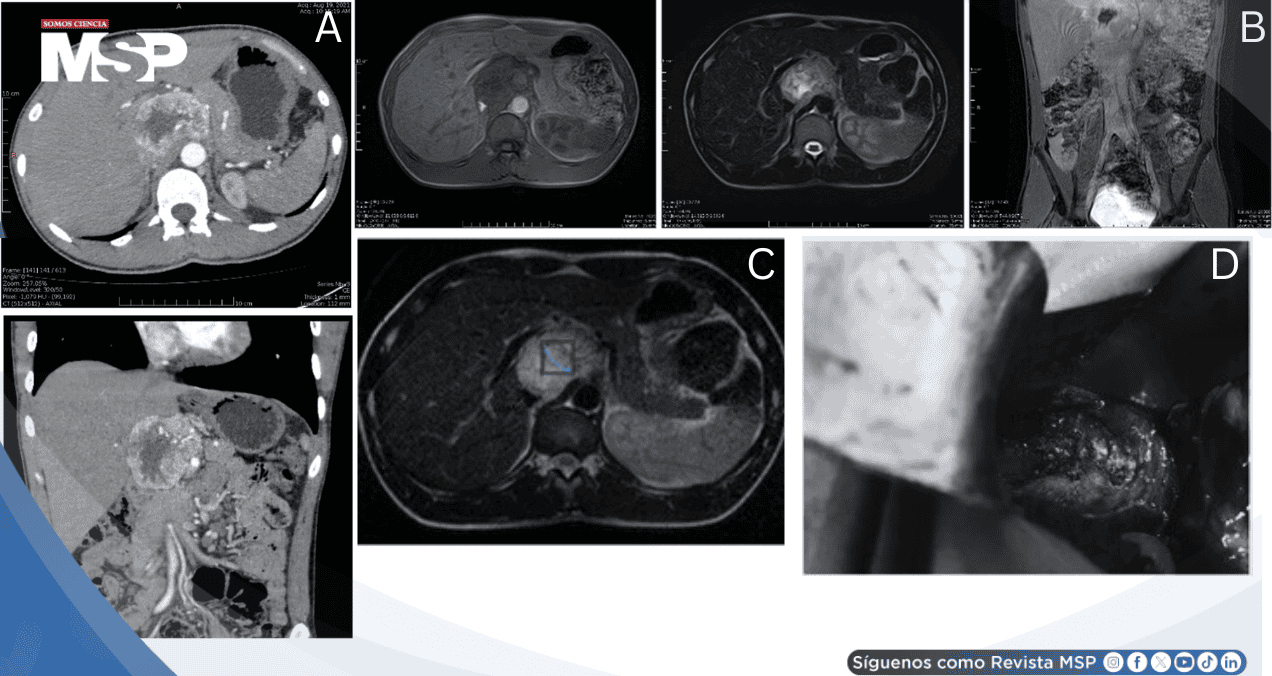

El plan inicial contemplaba abordaje laparoscópico, pero la evaluación intraoperatoria determinó conversión a cirugía abierta considerando el tamaño tumoral, su localización compleja y las estructuras vasculares circundantes.

Durante el procedimiento se identificó la ubicación anatómica precisa: anterior a la vena cava inferior, con la vena porta anteromedialmente y el páncreas inferiormente. La exploración confirmó ausencia de invasión, permitiendo resección completa exitosa.

El análisis histopatológico definitivo confirmó paraganglioma extra-adrenal. La evolución postoperatoria transcurrió sin complicaciones. Los controles bioquímicos a los 3 y 6 meses mostraron normalización completa de normetanefrina urinaria, con normalización tensional que permitió suspender medicación antihipertensiva.